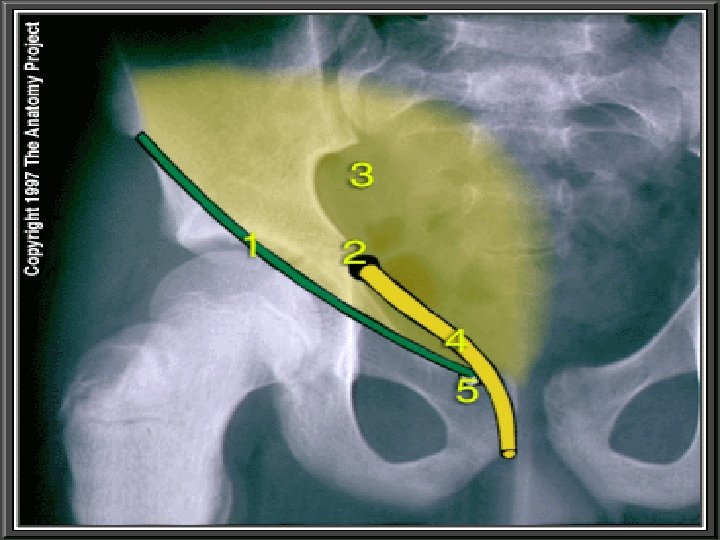

DEFINATION It is a musculo-aponeurotic tunnel which is placed obliquely just above the medial half of inguinal ligament in the lower part of anterior abdominal wall LENGTH 4 CM in length. Directed downwards forwards and medially. It is parallel to medial half inguinal ligament. Extends from deep inguinal EXTENT ring to superficial inguinal ring.

1. Anterior superior illiac spine 2. Pubic symphysis 3. Deep inguinal ring 4. Superficial inguinal ring 5. INGUINAL CANAL

– Oval gap in Fascia Transeversalis – 1. 2 cm above the midinguinal point – Structures entering through it • Spermatic cord along with internal spermatic fascia or • Round ligament of uterus

-Triangular gap in apponurosis of External oblique – Just above pubic crest. – Apex to base- 2. 5 cm – Structures passing through it • Spermatic cord along with internal spermatic fascia or • Round ligament • Ilio-inguinal nerve